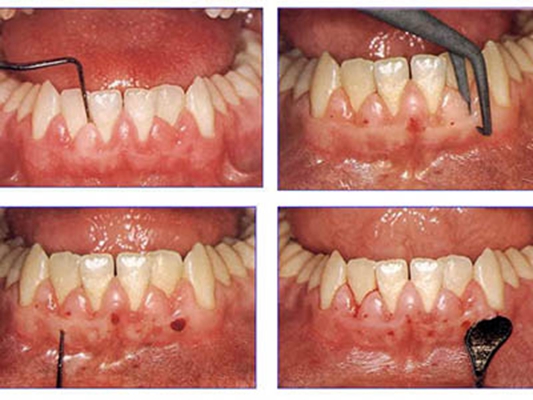

牙周炎圖片

牙周袋 (47)